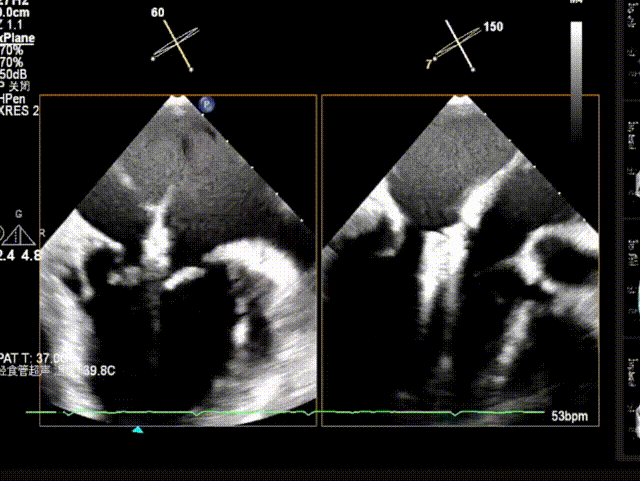

X-plane视窗可见二尖瓣2区脱垂;3D enface view示二尖瓣内P2脱垂,偏心性返流

反流束宽 15.4mm PISA半径 9mm,PISA 法估算EROA= 0.21cm²,Rvol=42ml

PW显示左肺静脉收缩期血流频谱呈逆向

3D模式测量二尖瓣瓣口面积5.57cm²;

二尖瓣口平均跨瓣压差=3 mmHg